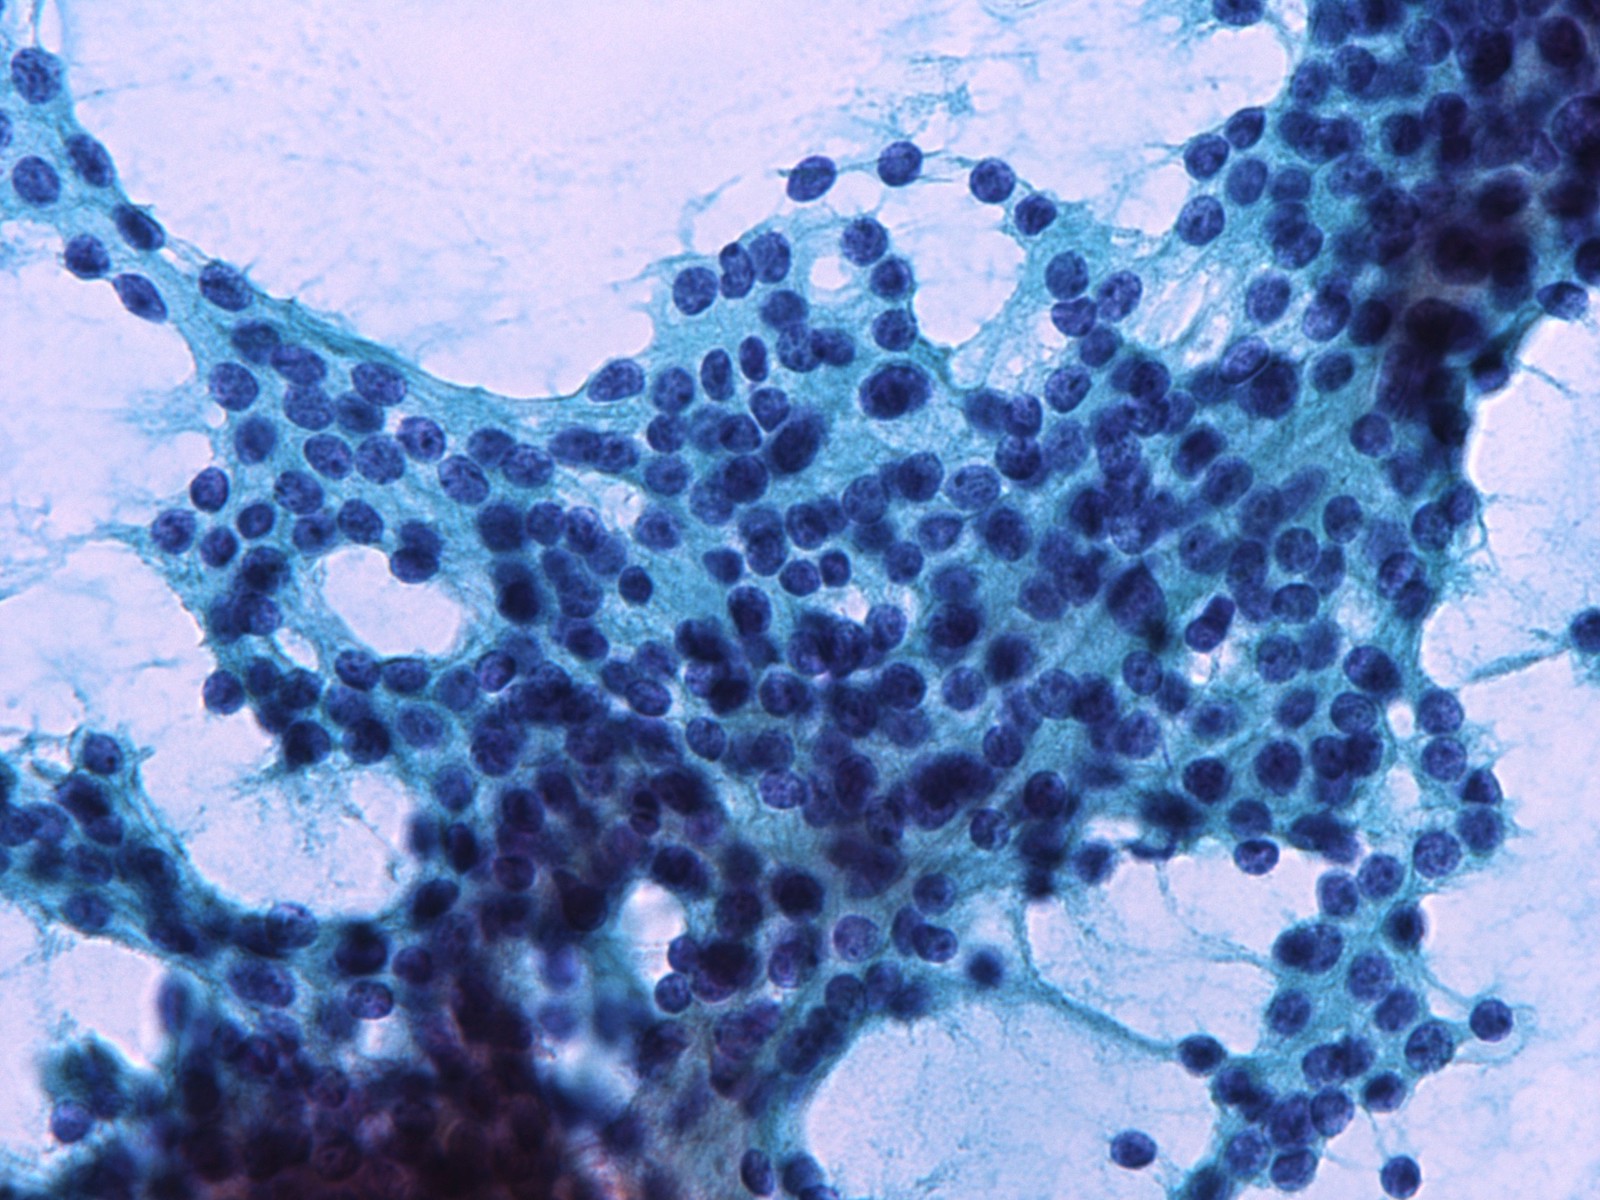

Cytology images

Contributed by Ayana Suzuki, Ph.D.

Images hosted on other servers: